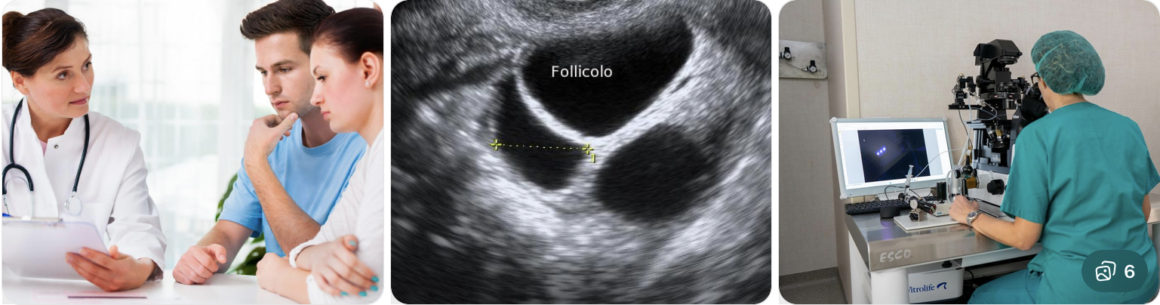

INFERTILITÀ FEMMINILE A PISTOIA

L’infertilità femminile è una condizione che può avere diverse cause e che richiede un’attenta valutazione specialistica.

Il Dott. Alessandro Errigo si occupa della diagnosi e del trattamento dell’infertilità femminile a Pistoia, offrendo un percorso completo e personalizzato.

Il percorso diagnostico comprende:

- visita ginecologica

- ecografia pelvica

- esami ormonali

Il trattamento viene definito in base al caso e può includere:

- terapie farmacologiche

- monitoraggio ovulatorio

- supporto alla procreazione assistita

L’obiettivo è accompagnare la paziente nel percorso verso la gravidanza con competenza e attenzione.